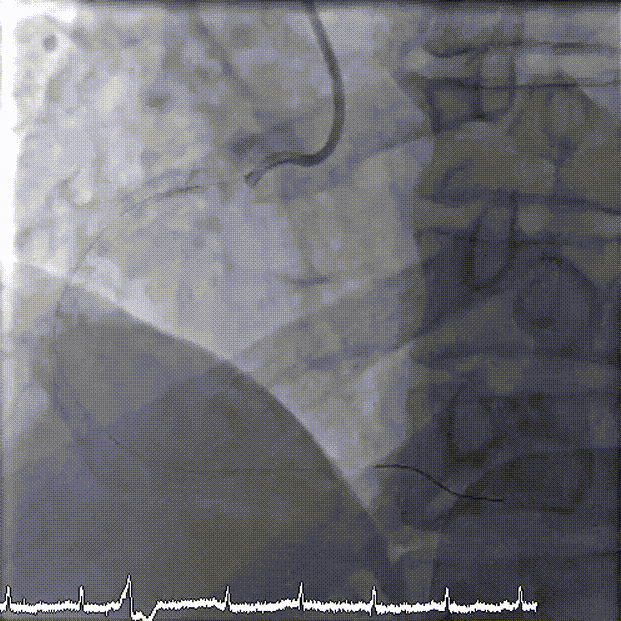

抽吸【例】量|【兑】话血栓抽吸